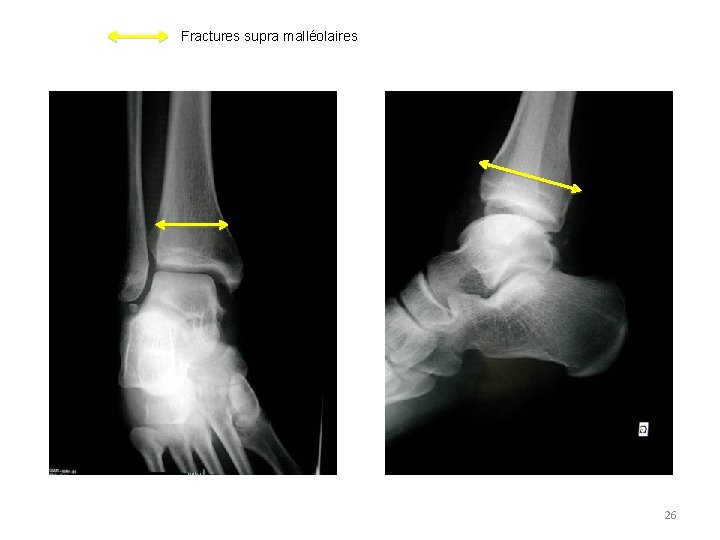

Fractures supra malléolaires 26

– Signes radiographiques • Traits de fracture – – Simple, comminutif Fracture Uni, bi, tri malléolaire (médiale, latérale, Destot) Fracture pilon tibial Fracture supra malléolaire • Déplacement, diastasis tibio – fibulaire, tibio – talien (indice de Skinner), luxation tibio – talienne associée • Problème du dépistage des lésions ostéo – chondrales du dôme talien associées Pas Facile en urgence Discussion du scanner 15